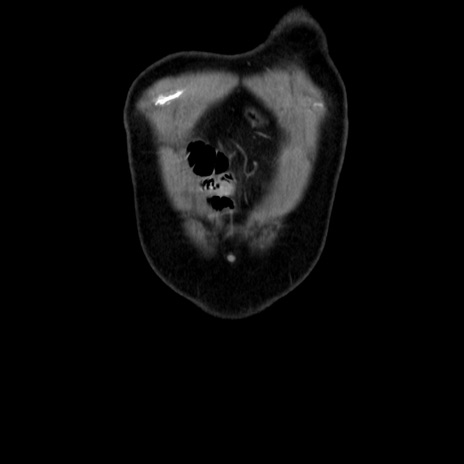

横断像

【症例】 70歳代男性

【主訴】 腹痛、嘔吐

【現病歴】 約1ヶ月前より間欠的に腹痛と嘔吐あり、当院消化器内科を受診したところCTで多発する肝臓のLDAを指摘され、精査中であった。以降は消化器症状は安定していたが、2日前より嘔気と腹痛があり、同日より排便・排ガスが消失した。改善認めず、 本日、救急外来を受診した。